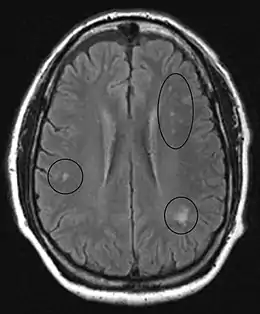

In the brain itself, changes are less severe: They occur as small sources of nervous fibers decay and accumulation of astrocytes, usually subcortically located, and also round hemorrhages with a torus of glial cells.

MRI of the brain may show periventricular white matter abnormalities. MRI of the spinal cord may show linear hyperintensity in the posterior portion of the cervical tract of the spinal cord, with selective involvement of the posterior columns.